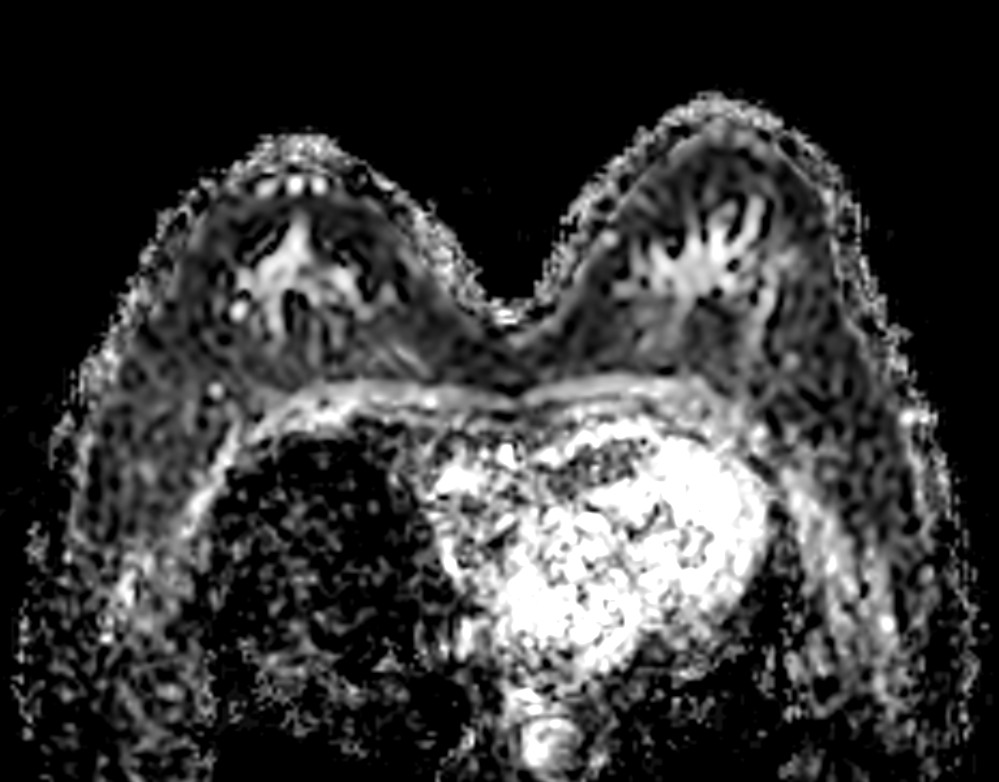

Axial DWIBS ADC